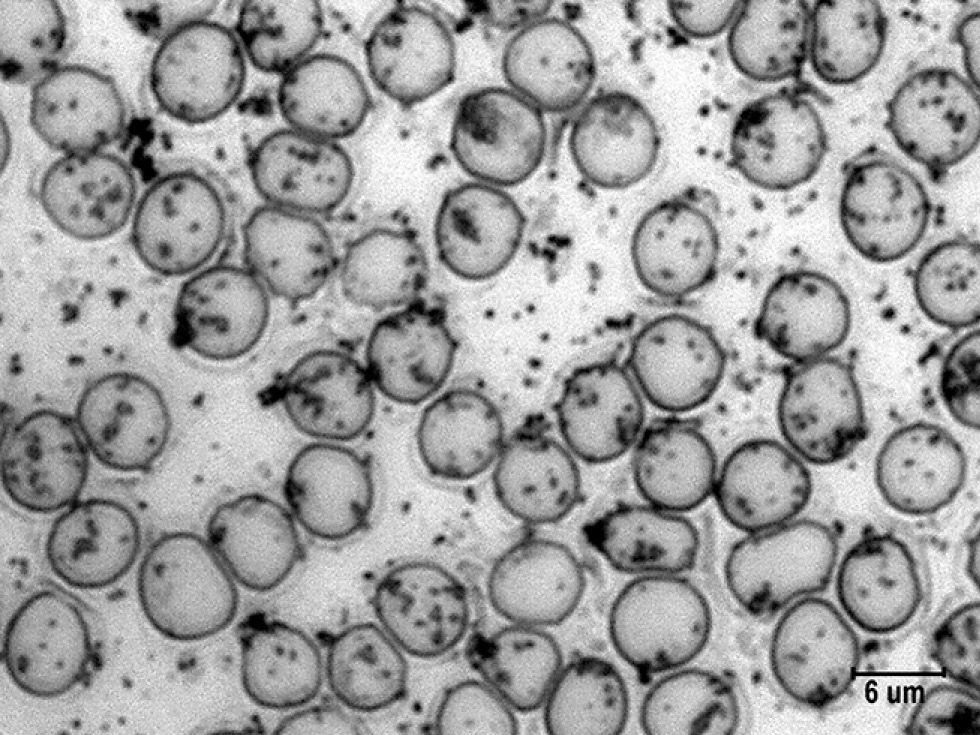

Введение препарата, стимулирующего НАС и обмен катехоламинов, отразилось на их связывании эритроцитами. Согласно рис. 4 и табл. 3, общее число гранул катехоламинов оказалось равным 117±8,4 шт., что ниже контрольного на 20% (р <0,1). Такое сокращение общего числа гранул определялось уменьшением количества малых гранул на 35% и средних на 29,2%, число крупных гранул не изменилось.

Рис. 4. Гранулы катехоламинов на поверхности эритроцитов в мазках крови крыс на фоне стимуляции норадренергической системы. Импрегнация азотнокислым серебром с докраской эозином. Ув. ×4000. / Fig. 4. Granules of catecholamines on the surface of erythrocytes in the blood smears of rats during the stimulation of the noradrenergic system. Impregnation with silver nitrate and final staining with eosin. Magnification. ×4000.